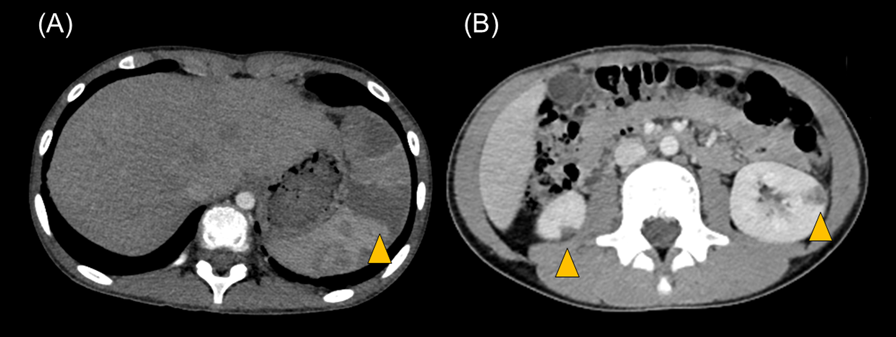

Transthoracic echocardiography revealed multiple vegetations in the aortic arch (Fig. 1). Thoracic contrast-enhanced CT indicated not only SVAS but also stenosis at the origin of either the brachiocephalic artery or the left common carotid artery (Fig. 2). At the time of admission, the patient also experienced left-sided abdominal pain and nausea. Abdominal contrast-enhanced CT revealed renal and splenic infarctions without any arterial aneurysm (Fig. 3). Magnetic resonance imaging (MRI) revealed a very small brain hemorrhage scar. Blood culture detected Abiotrophia defectiva, an endemic oral bacterium that shows penicillin sensitivity. We made a diagnosis of IE according to the modified Duke criteria.4) Urgent surgery for removing vegetations was performed to avoid cerebral embolisms, followed by antibiotic therapy using both penicillin 300,000 U/kg/day and Gentamycin 3 mg/kg/day.

Fig. 3 Abdominal contrast-enhanced CT shows (A) splenic and (B) renal infarction

The arrow heads indicate the areas of infarction.